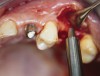

At the time of surgery, local infiltrative anesthesia was administered (lidocaine 2% with epinephrine, 1:100,000). A full-thickness mucoperiosteal flap was raised. The initial osteotomy was performed on midcrestal bone using a rose-headed bur. To prepare the osteotomy site for implant placement, sequential alternating osteotomes with variable conicity were used, drilling 2-mm shorter than the length of the implant to be placed (Figure 3A and Figure 3B). The implants presented initial primary stability (Figure 4), the cover screws were placed, and the implants were submerged for a healing period. The tissue was approximated, and the patient was instructed not to wear any denture or to place pressure on the healing site.

Figure 3A and Figure 3B Alternating osteotomes with variable conicity used to perform the alveolar remodeling in the area of tooth No. 24.

Figure 3a  Alternating osteotomes with variable conicity used to perform the alveolar remodeling in the area of tooth No. 24.

Figure 3a

Figure 3b  Alternating osteotomes with variable conicity used to perform the alveolar remodeling in the area of tooth No. 24.

Figure 3b